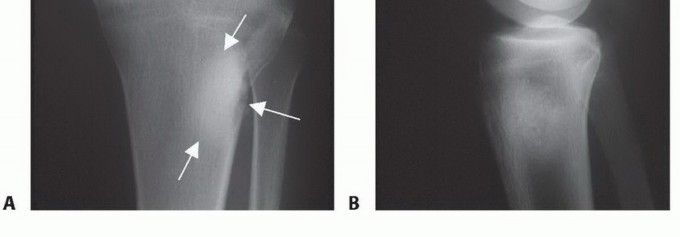

يُعد التصوير المقطعي المحوسب (CT) والتصوير بالرنين المغناطيسي (MR) أدوات لا غنى عنها لتحديد مدى تدمير القشرة العظمية، والامتدادات داخل النخاع العظمي، وامتدادات الورم في الأنسجة الرخوة المحيطة. هذه البيانات حيوية لتحديد مستوى استئصال قصبة الساق، والذي يكون عادةً 3 إلى 5 سم بعيداً عن منطقة إصابة الورم داخل النخاع.

يمكن للتصوير بالرنين المغناطيسي أيضاً الكشف عن "الآفات القافزة" (skip lesions)، وهي بؤر ورمية منفصلة عن الورم الرئيسي، والتي قد تؤثر على مدى استئصال قصبة الساق. يوفر الأستاذ الدكتور محمد هطيف تحليلاً دقيقاً لهذه الصور لضمان تحديد هامش جراحي آمن وفعال.

صورة شعاعية توضح ورماً عظمياً في قصبة الساق القريبة.

صورة شعاعية جانبية توضح ساركوما عظمية في قصبة الساق القريبة.

صورة شعاعية تظهر تدميراً قشرياً وامتداداً للأنسجة الرخوة للورم.

صورة مقطعية توضح تدميراً قشرياً وامتداداً للأنسجة الرخوة للورم.